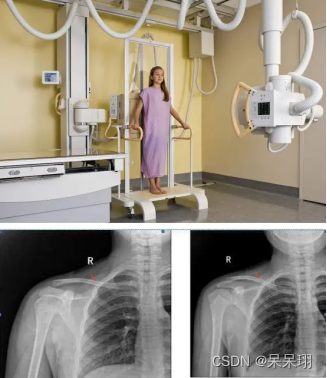

2. DR(数字X射线摄影)

1. 概念:DR是数字化X射线摄影技术,用于捕捉和显示X射线图像。它取代了传统的胶片摄影,数字图像可以立即显示和存储。

2. 优点:

- 高分辨率:DR可以提供高分辨率的X射线图像,有助于准确诊断。

- 实时性:DR图像可以立即显示,医生可以即时进行观察和分析。

- 图像处理:数字化的图像可以进行后期处理和增强,有助于改善图像质量。

3. 缺点:

- 需要辐射:DR仍然需要使用X射线,尽管辐射剂量相对较低,但仍有一定的辐射风险。

- 无法提供三维信息:DR主要提供二维图像,无法提供像CT和MRI那样的三维信息。

4. 应用:DR广泛应用于骨骼系统、胸部、牙科等检查,如骨折诊断、肺部疾病筛查、牙齿拍片等。